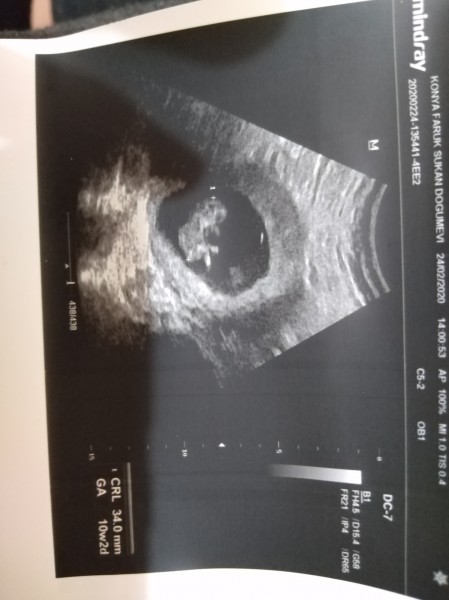

Cinsiyet tahmini yaparmısınız lütfen

Kızlar kusura bakmayın merak işte Allah bilir ama

Gebelik haftası

10+4

Erkek bence baya tecrubelendim bu konuda içimden geçme veya kese şekli değil bebegin poposuna bakıyorum benim 12 haftalıkken doktor kiza benziyor dedi ultraosna Bak tim erkek kesin dedim pipi var düyek yaptım 12 +4 de durmuş kalp atışı erkekti gördüm bebişim tahminim doğru çıktı bu daha çok küçük genelde kız sa bu haftalarda korkdon olunca erkeğe nediyor diyorlar ilerki haftalarda kiza dönüyor yani tahmin için çok erken canım bacak arası çekmesi tam net gözükmüyor ama tahminim erkek